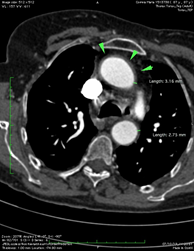

Blood tests revealed no changes, except an Erythrocyte sedimentation rate (ESR) of 56m, and C-reactive protein (CRP) of 44 mg/L. Plasma and urinary catecholamine levels were within the reference values. The autoimmunity study was negative. The electrocardiogram showed sinus rhythm, with a heart rate of 73 beats per minute, with no changes in rhythm, conduction, or ventricular repolarization. The 24-hour Holter confirmed the baseline sinus rhythm and some periods of 2nd-degree atrioventricular block Mobitz I during sleep. To complete de cardiac study, an echocardiogram was performed, which revealed mild mitral-aortic degenerative changes, aortic valve fibrosis, mitral ring calcification, mild regurgitation, and an enlarged left atrium. For the absence of palpable pulses, an Arterial Eco-Doppler of the Upper Limbs was performed, revealing a significant stenosis of the axillary arteries bilaterally, more severe on the right and with distal hemodynamic compromise. To exclude a Giant Cell Arteritis a Cerebral Vessel Wall MRI was performed and excluded changes in the temporal artery. Lastly, the Thoracic and Abdominal Angio-CT showed a diffuse thickening of the aorta wall, (Figure 1), stenosis of the left subclavian artery (Figure 2 & 3) with an inflammatory component, reduction in the caliber of the right subclavian artery and severe stenosis of the renal artery (Figure 4), thus suggesting a Takayasu Disease.

Figure 1 On axial Angio-CT slice, Diffuse thickening of the ascendent and descending aorta are indicated by green arrowheads and green line.

Figure 2 On axial Angio-CT slice, stenosis of the left subclavian artery with an inflammatory component is indicated by green arrows.